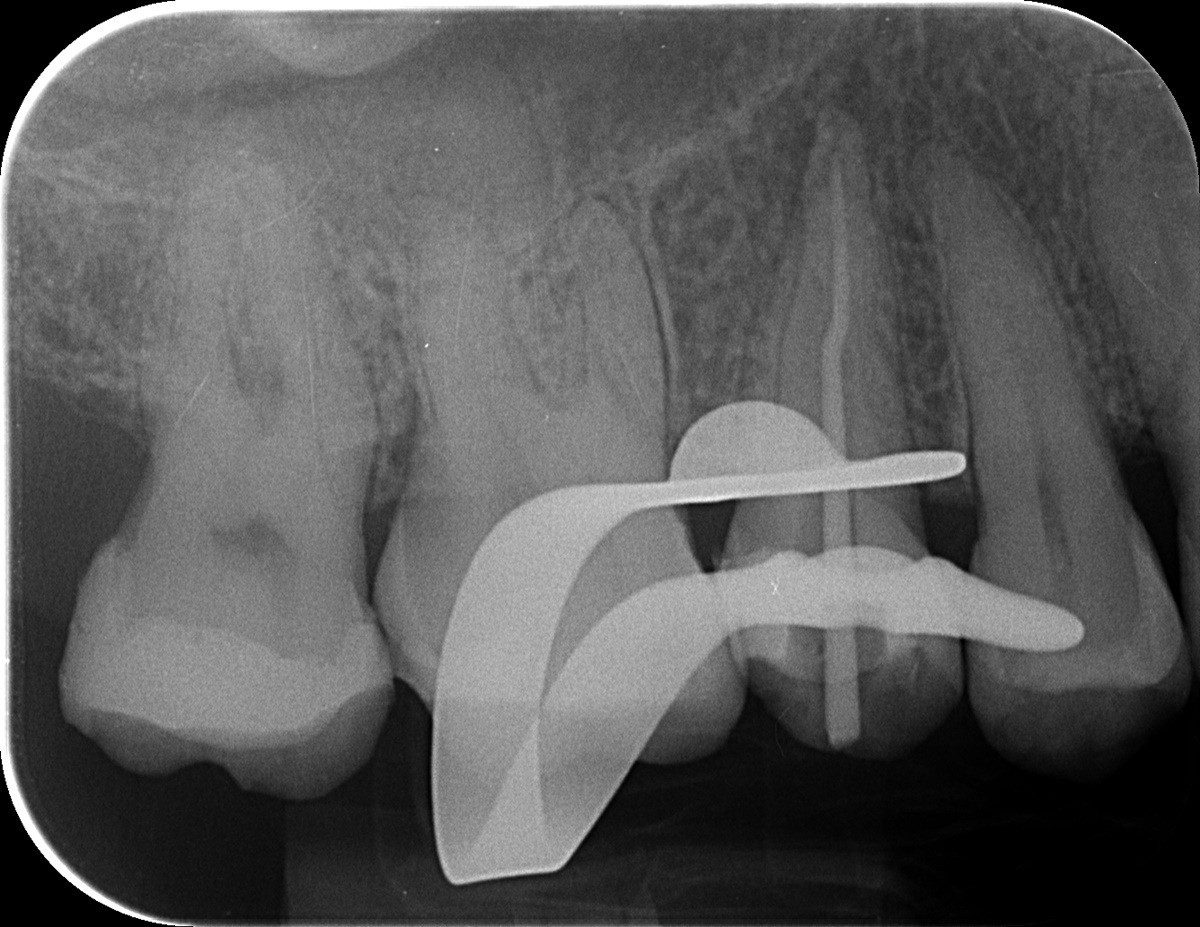

Kis korrekció, és egy ismételt fertőtlenítési protokoll után pedig elkészítettük a gyökértömést. A kezelés még egy alkalmat vett igénybe, az ún. üvegszálas csapos megerősítést ekkor helyeztük a fogba. Ez egyfajta belső merevítésül szolgál, védi a maradék foganyagot a későbbi törésektől, illetve viseli a koronát, ami pár hét után készül majd a fogra. A gyökértömést követően páciensünk szinte teljesen tünetmentes volt, a szokásos, pici érzékenységen kívül fájdalmai, panaszai nem voltak. Izgatottan várjuk az első, 3 hónap múlva esedékes kontroll időpontját, ahol majd láthatjuk a gyökércsúcson elhelyezkedő gyulladás gyógyulását is!

mikroszkópos gyökérkezeléssel megmentett fog: a bent rekedt fragmentumok eltávolítása 5